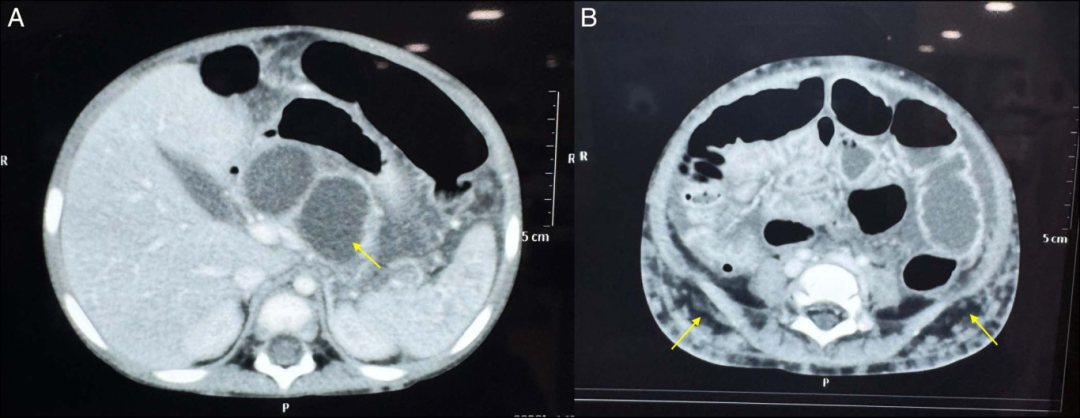

图2 (A)CT扫描显示急性坏死性胰腺炎,实质被大片坏死组织取代(黄色箭头)。(B)CT扫描显示腹部两侧显著的皮下脂肪坏死(黄色箭头)